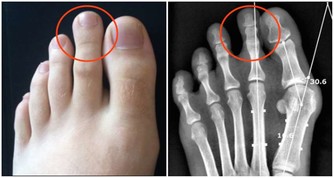

3.骨質密度

人的骨質密度和營養、發育、遺傳等因素影響,一般從35歲開始,骨質密度開始下降,尤其女人在絕經後5年內,骨量缺失最快。

除了藉由骨質密度檢測了解之外,平時應該不挑食,藉由吃豆腐、蝦皮、喝牛奶等方式攝取鈣和維生素D,同時要運動、曬太陽,預防比治療,食補勝過藥物,更有效果。